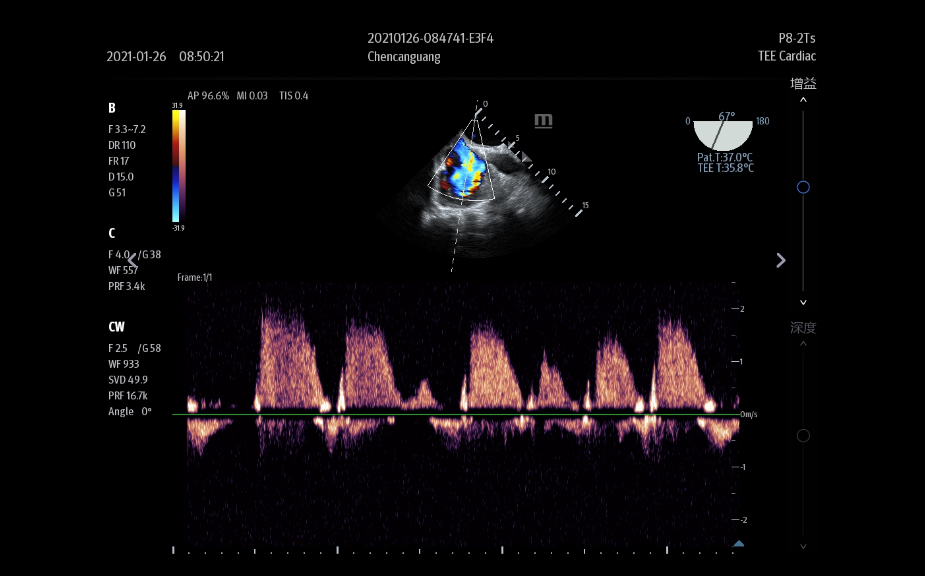

L'├®chographe TE9 a ├®t├® con?u pour faciliter les soins et ├®tendre les capacit├®s d'imagerie pour lŌĆÖanesth├®sie, les urgences et les soins intensifs. Gr?ce ├Ā ses fonctions avanc├®es, son grand ├®cran tactile et sa technologie d'imagerie sup├®rieure, l'├®chographe TE9 permet d'am├®liorer l'efficacit├® clinique et dŌĆÖassurer un diagnostic en toute confiance. Gr?ce ├Ā des outils dŌĆÖacquisition et de calculs automatiques, les soignants peuvent obtenir des mesures rapides et reproductibles dans le cadre d'examens et proc├®dures fiables, m├¬me dans des environnements o├╣ le rythme est soutenu.